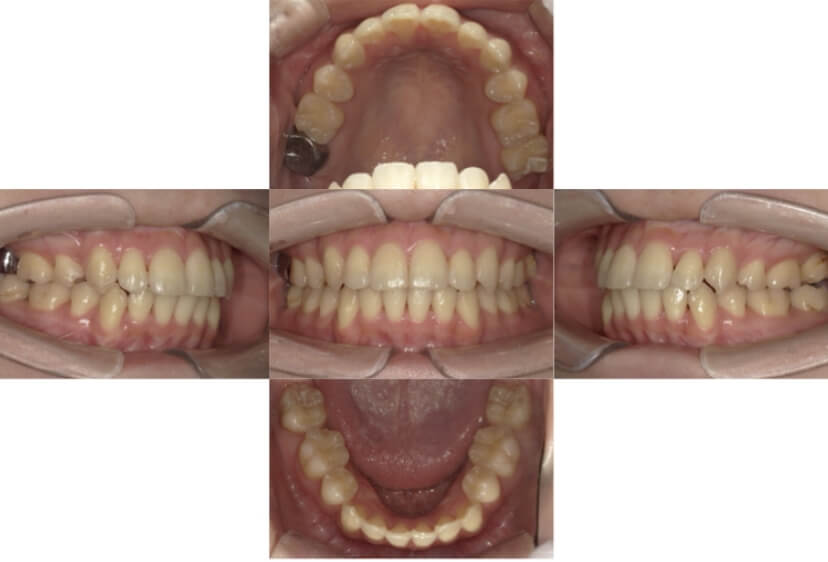

症例4

下顎前突、叢生

抜歯

ブラケット矯正

上下顎叢生、反対咬合(上下の前歯のガタガタ、若干受け口)のケースです。

装置はラビアル(上下表側)で、上下顎の小臼歯を4本抜歯を行っています。抜歯したスペースを使って、上下の叢生改善と前歯の受け口の改善を行っています。

主訴 前歯のガタガタを治したい。

年齢・性別 45歳 女性

お住まいの地域 神奈川県川崎市

治療方針 抜歯スペースを利用して上前歯の叢生(ガタガタ)の改善と受け口の改善

抜歯部位 上顎左右第一小臼歯、下顎左右第二小臼歯

使用装置 ラビアル(上下表側)、顎間ゴム

治療期間 2年6か月

治療回数 20回

リテーナー クリアリテーナー

BEFORE

AFTER